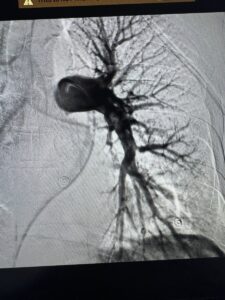

Під рентгенконтролем через судини катетером ми дісталися тромбів й видалили їх спеціальною системою аспірації.

Це перші успішні тромбаспірації при ТЕЛА, виконані у нашому об’єднанні.